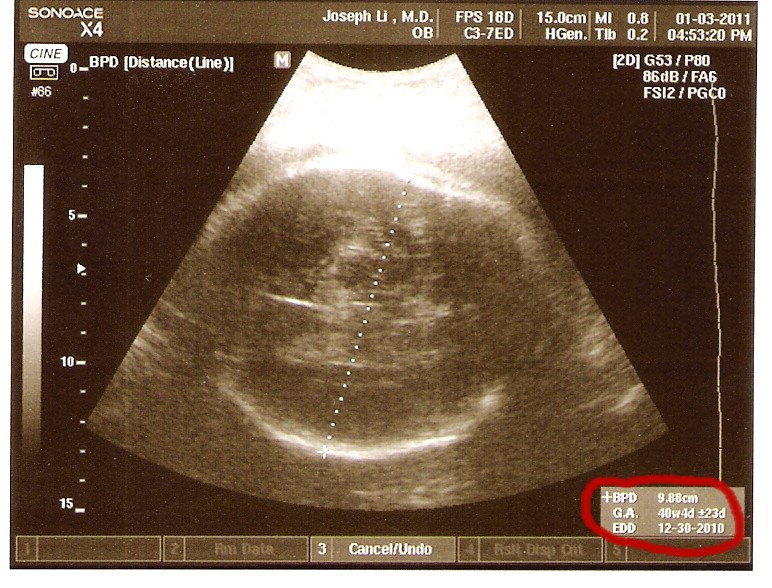

So these are the last two US pics I will have of you (I think I may have about 100 of them). I wanted them here so you could see.

When these scans were taken we were at 39 weeks in the pregnancy.

Your head circumference measures large enough to put you at 40 weeks and 4 days and a due date of 12/30/10. You femur measurement puts you at 39 weeks with a due date of 1/10/11.

So that makes you tall and skinny with a BIG head. Just like your brother.